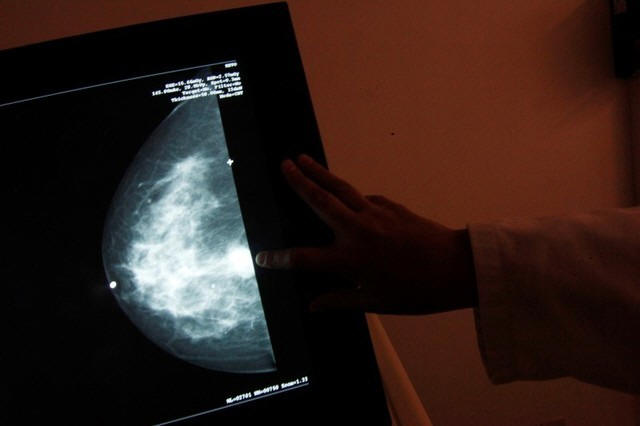

Under the U.S. Preventive Services Task Force guidelines, mammogram

screening every two years for women 50 to 74 got a grade of "B",

meaning doctors should offer the service. Screening for women in

their 40s got a "C" grade, meaning doctors should offer the service

for select patients, depending on individual circumstances.